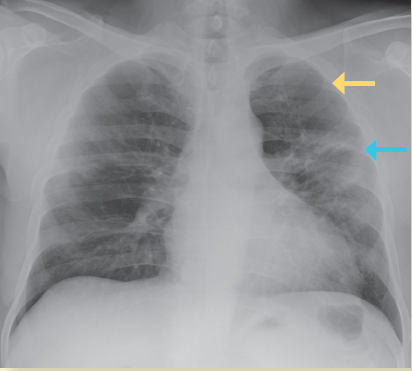

Radiografía

Se ha reportado que la sensibilidad de la radiografía de tórax es de 69%, menor respecto del RT-PCR, el cual es de 91%, aunque se observaron casos en que las anormalidades radiográficas preceden a los estudios de RT-PCR positivos en un 9% de los casos. Los hallazgos radiográficos más comúnmente encontrados son: consolidación, imagen en vidrio despulido, de distribución periférica y en las zonas inferiores, con un involucro bilateral (50%), mientras que el derrame pleural es poco común (3%); los hallazgos radiográficos tienen un pico de aparición a los 10-12 días del inicio de los síntomas9 (figura 1).

Imagen: Muñoz Jarillo et al.

*Nótese la menor atenuación del patrón en vidrio despulido que permite la visualización de las estructuras vasculares.

Figura 1 Radiografía de tórax PA donde se observan áreas en vidrio despulido (flecha amarilla) con áreas de consolidación de distribución periférica (flecha azul)